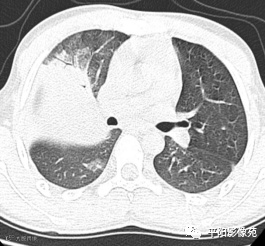

10天后再次复查CT:较前有所好转

①充血期:X线无阳性征象或仅表现为局限性肺纹理增粗;CT表现为边缘模糊的磨玻璃样阴影。②实变期:整个肺叶、大部分肺叶或肺段呈高密度阴影,阴影密度均匀,内可见支气管充气征,肺叶实变以叶间裂为界,边缘清楚。③消散期:大叶阴影密度减低,逐渐变为散在斑片状阴影,进而演变为索条状阴影,直至完全吸收。